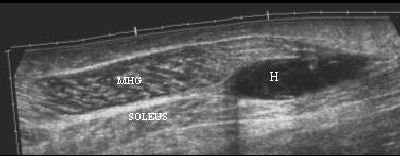

![]() |

| Tennis leg-related hematoma on ultrasound. Image courtesy of Dr. Ronald Adler, Hospital for Special Surgery, New York City. |